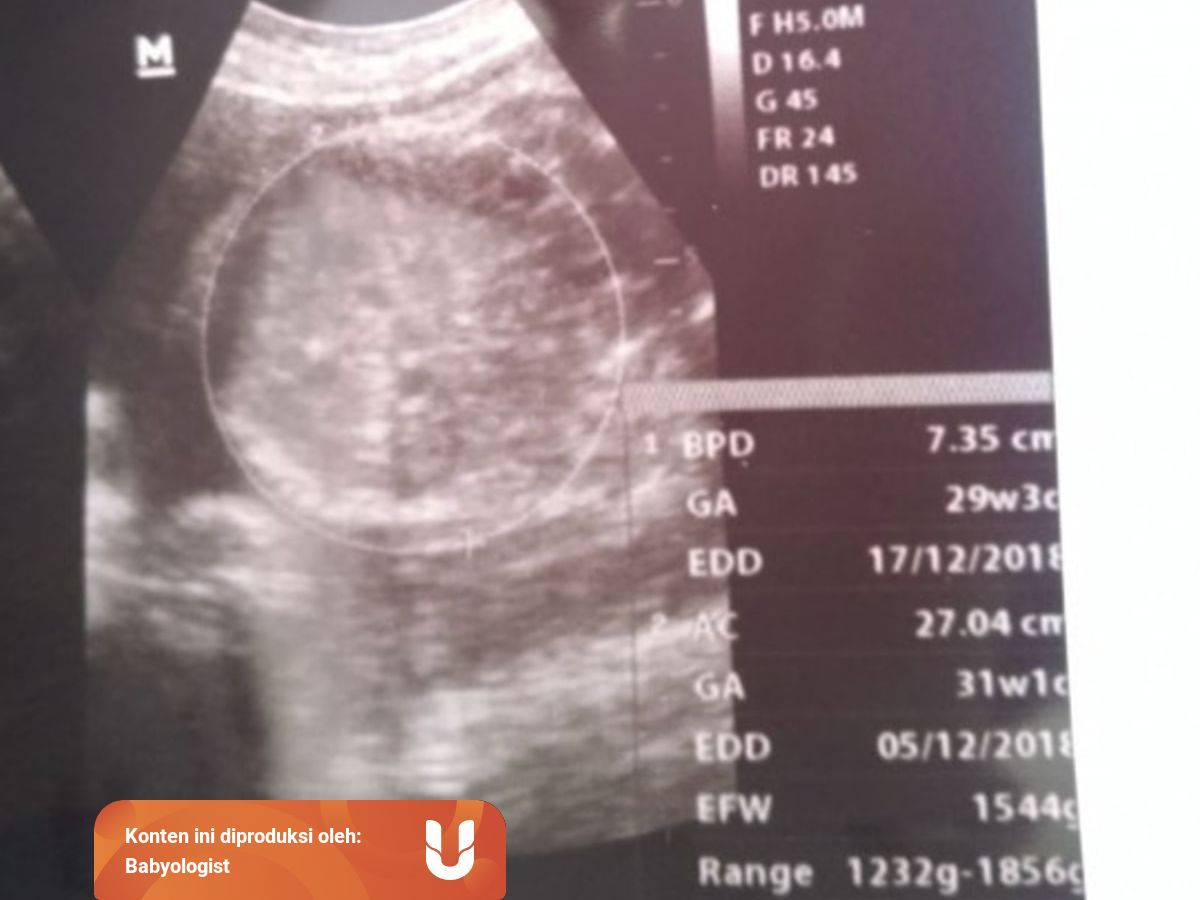

Hasil USG saya saat itu. Biparietal diameter is used to estimate fetal weight and gestational age. 834 34w0d FL.

Tentunya ukuran setiap janin bisa berbeda. 2143 g 33w6d Tiap USG ukuran BPD FL AC dan berat janin kurang dari usia sebanyak 2-3 Minggu. 2906 33w0d EFW.

Taksiran berat janin sekitar 13kg. BPD 886 AC 319 FL 665 TBJ 2600-2700 gr Normalkah itu dok. Cara Membaca Gambar Hasil USG Bayi untuk Jenis Kelamin.

Untuk lingkar kepala bayi atau BPD sendiri antara usia 33-37 minggu dapat berkisar antara 83-95 cm pada kondisi saat ini bisa sedikit lebih besar dari normal. Persalinan yang normal umumnya terjadi saat usia kandungan 37-42 minggu kurang dari 37 minggu prematur 42 minggu postmatur. BPD umumnya digunakan untuk mengukur janin saat memasuki trimester dua atau tiga.